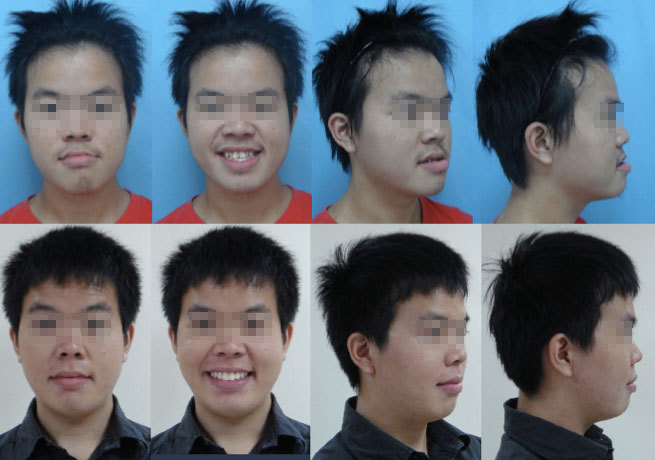

Case A: 有沒有牙齒進行隱形矯正後,原本戽斗+嘴型不正的臉型改變了,覺得整個變陽光,更有朝氣,更討人喜歡呢?

牙齒矯正前口內照

牙齒矯正後口內照